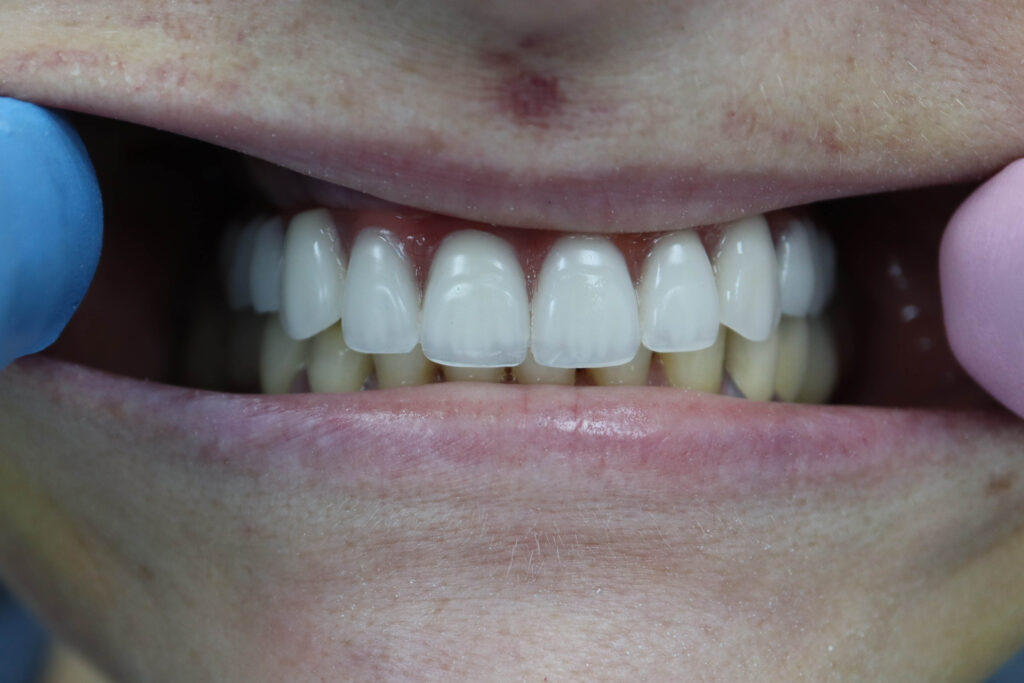

Пациент обратился с жалобами на эстетические недостатки. Диагноз: частичная вторичная адентия на верхней челюсти.

Зубы на верхней челюсти в неудовлетворительном состоянии.

Было произведено удаление зубов на верхней челюсти и проведена комплексная имплантация по системе All-on-6.

Установлены 6 имплантатов Megagen AnyRidge.

Спустя 7 дней на верхней челюсти зафиксирован временный металлоакриловый протез из 12 зубов.